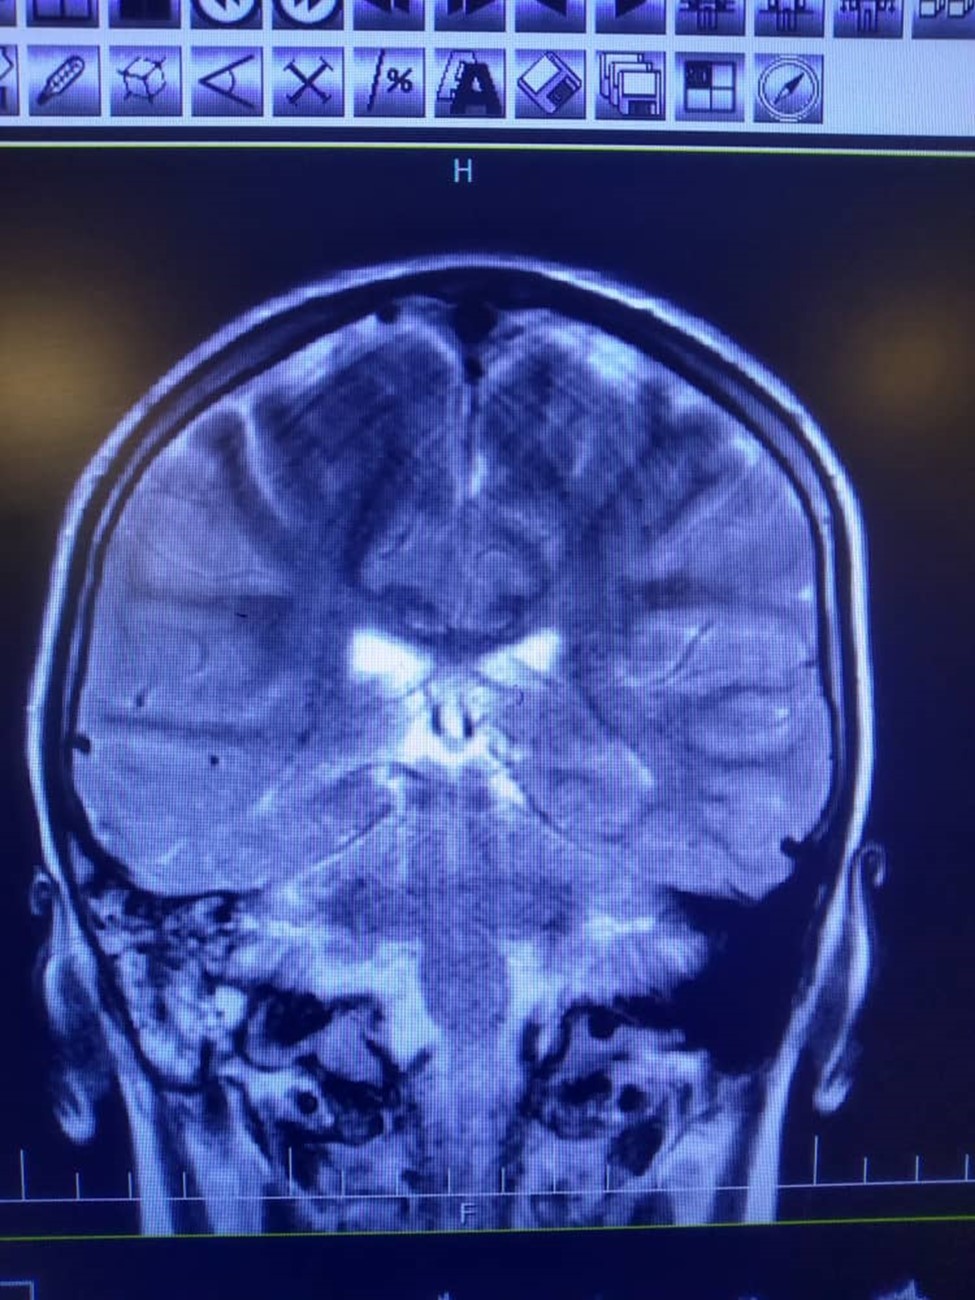

Figure 2.High signal intensity in both hemispheres is noted suggestive of meningitis. In T2 sequence there are hyper signal material left maxillary sinuse and bilateral frontal sinuses in favour of sinusitis, polyp and retention cyst in left maxillary sinus is noted. Effusion in right mastoidal air cell is noted.